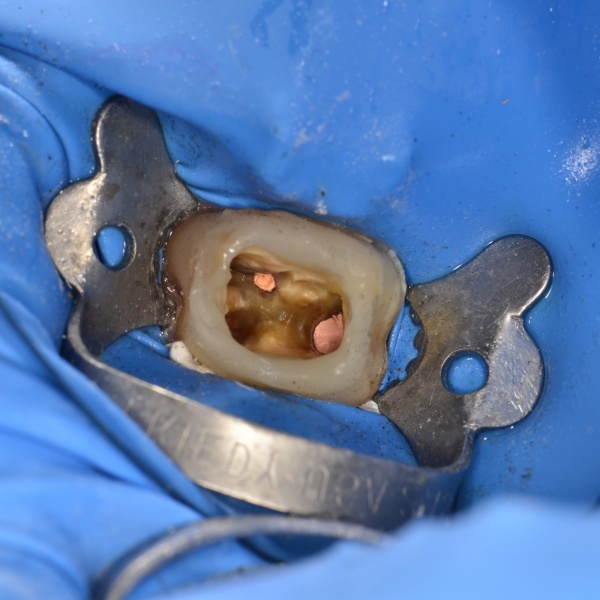

Ošetření kořenových kanálků (primární i sekundární)

10. 11.

16:00 - 18:00   MDDr. Jakub Váša

Co vás čeká?

Endodoncie je velmi komplexní ošetření, který dokáže neustále překvapovat. Každý zub, každý kořenový systém je svým způsobem specifický.

Probereme zásadní kroky moderní endodoncie nutné pro úspěšné ošetření:

• trepanace

• mechanické opracování

• chemické opracování

• plnění

Zaměříme se na časté chyby a jak jim předcházet.

V rámci reendodoncie si řekneme, jak nejlépe odstranit všechny možné výplňové materiály, se kterými se můžeme v kořenovém systému potkat. Probereme také:

• na co si dát pozor v rámci tvrdých zubních tkání

• jak co nejlépe připravit zub na kvalitní postendodontické ošetření

Vše bude doplněno množstvím obrazového materiálufotky, rentgeny, videa.